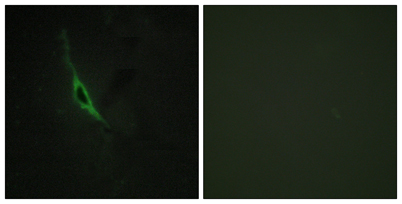

Granzyme K rabbit pAb

Product name: Granzyme K rabbit pAb

Dilutions: Western Blot: 1/500 - 1/2000. Immunohistochemistry: 1/100 - 1/300. Immunofluorescence: 1/200 - 1/1000. ELISA: 1/20000. Not yet tested in other applications.